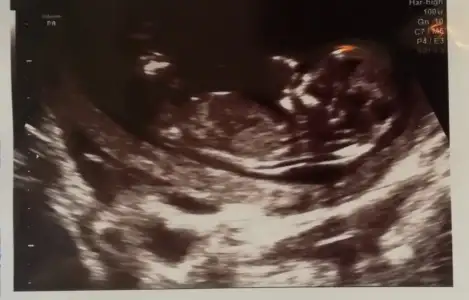

Kız sanki emin olmadım çok net değil usg varsa 11 yada 13 hafta usg olursa paylaşınSelam canlar, anlayan varsa bize de bakabilir mi acaba![]()

Erkek gibi 12-13 hafta olursa tekrar usg paylaşınBenimkini de tahminde bulunabilecek var mı 11. Hafta :))